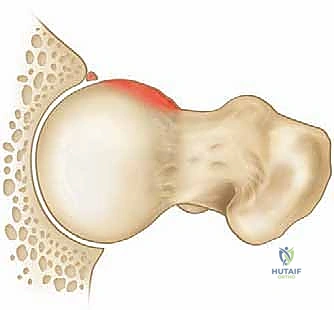

يُغلف كل من الكرة والتجويف بطبقة ناعمة جداً تُسمى الغضروف المفصلي، والتي تسمح للعظام بالانزلاق بسلاسة تامة. بالإضافة إلى ذلك، يُحاط التجويف بحلقة من غضروف ليفي قوي تُسمى الشفا الحقي (Labrum). يعمل الشفا كختم مطاطي (O-ring) يحافظ على السائل الزلالي داخل المفصل، ويزيد من استقراره. في حالة انحشار الفخذ الحقي، يكون هذا الشفا هو الضحية الأولى للاحتكاك العظمي.

يحدث هذا النوع عندما لا يكون رأس عظم الفخذ كروياً بشكل مثالي. بدلاً من ذلك، تتكون نتوءات عظمية إضافية عند منطقة التقاء رأس وعنق الفخذ. هذا الشكل غير الدائري يجعله يحتك بقوة بحافة التجويف (الحُق) أثناء الحركة، مما يؤدي إلى "كشط" وتمزيق الغضروف والشفا الحقي. هذا النوع شائع جداً بين الشباب والرياضيين الذكور.

2. انحشار الكماشة (Pincer Impingement)

3. الانحشار المختلط (Mixed Impingement)

وهو النوع الأكثر شيوعاً على الإطلاق، حيث يعاني المريض من كلا التشوهين في وقت واحد (الكامة والكماشة). يتطلب هذا النوع مهارة جراحية استثنائية لإعادة نحت كل من عظم الفخذ والحوض في نفس العملية.